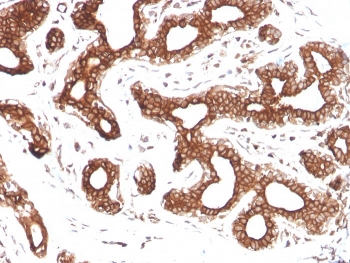

IHC staining of FFPE human breast carcinoma with Calpastatin antibody (clone CAST/1550). HIER: boil tissue sections in pH 9 10mM Tris with 1mM EDTA for 20 min and allow to cool before testing.

IHC staining of FFPE human prostate carcinoma with Calpastatin antibody (clone CAST/1550). HIER: boil tissue sections in pH 9 10mM Tris with 1mM EDTA for 20 min and allow to cool before testing.

IHC staining of FFPE human colon carcinoma with Calpastatin antibody (clone CAST/1550). HIER: boil tissue sections in pH 9 10mM Tris with 1mM EDTA for 20 min and allow to cool before testing.

IHC staining of FFPE human bladder carcinoma with Calpastatin antibody (clone CAST/1550). HIER: boil tissue sections in pH 9 10mM Tris with 1mM EDTA for 20 min and allow to cool before testing.